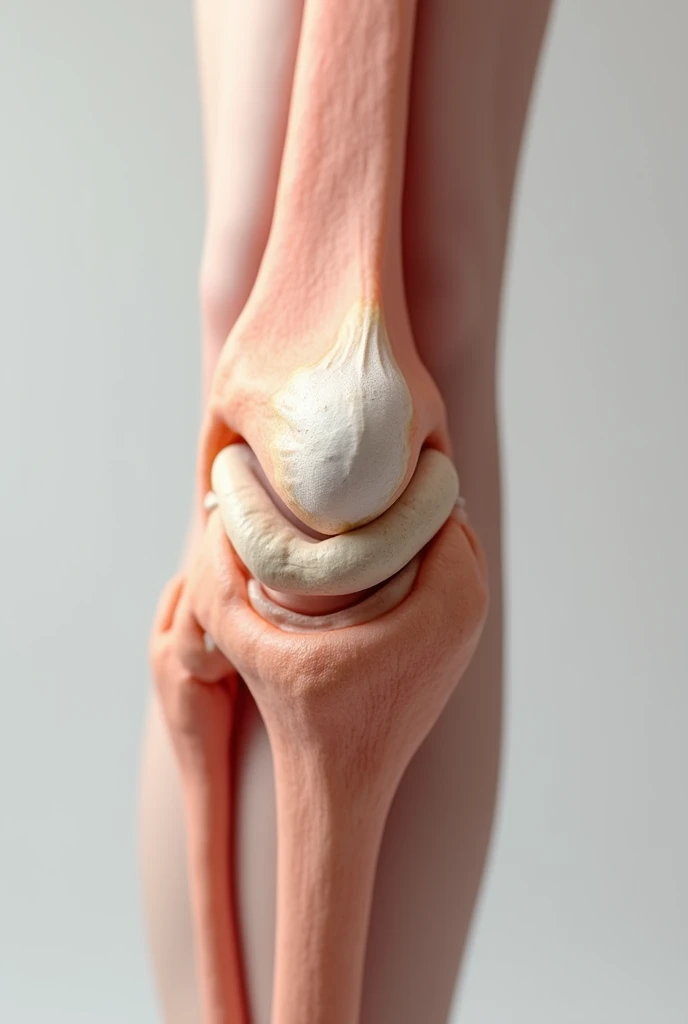

Close-up of human knee,There is a bone in the middle, knee, Knees, surreal bone structure, Protruding bones, Realphotos, orthographic view, Look across the shoulder, medical depiction, Osteoarticular joints, computer generated, hyper realisitc, sharp bone structure, joint, digital painted

Close-up of human knee

surreal bone structure

Protruding bones

medical depiction

Osteoarticular joints

hyper realisitc

sharp bone structure